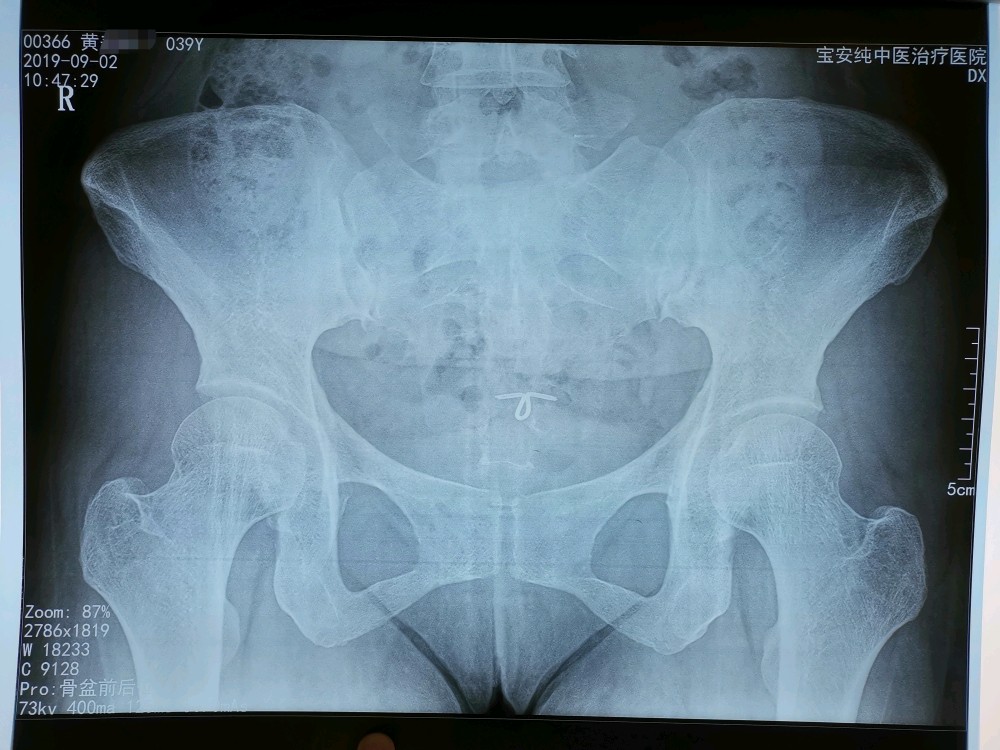

影像:自带腰椎CT未见异常。拍站立位骨盆平片示:双侧髂骨翼不对称,耻骨联合不等高。

诊断:骶髂关节错缝

齐伟主任指出:患者在正规三甲医院按腰椎间盘突出症治疗一个月无效,首先置疑“诊断”的正确性。自带腰椎CT片未见明显间盘突出和神经根受压,更加怀疑“诊断”的可靠性。查体时患者腰部无明显压痛及放射性疼痛,直腿抬高时无下肢放射性疼痛,无皮肤感觉障碍,跟膝腱反射正常,故否定“腰椎间盘突出症”的诊断。“右侧直腿抬高30度时臀部剧痛、下肢无疼痛”为直腿抬高试验假阳性,并非直腿抬高30度,是骶髂关节及臀部肌肉疼痛限制的结果,屈膝屈髋试验可以证实,真阳性为腰及下肢的牵扯性疼痛。右侧臀大肌、臀中肌僵硬,压痛(+),向小腿外侧放射,右侧直腿抬高及屈膝屈髋时臀部剧痛,无下肢放射性疼痛,右足外旋多于左侧,右侧“4”字试验(+),拟诊断为“骶髂关节错缝、臀大肌损伤、臀中肌损伤”。针刀正骨治疗一次后症状明显减轻,验证了“拟诊断”的可靠性,方向正确,效不更方,故能三次而愈。